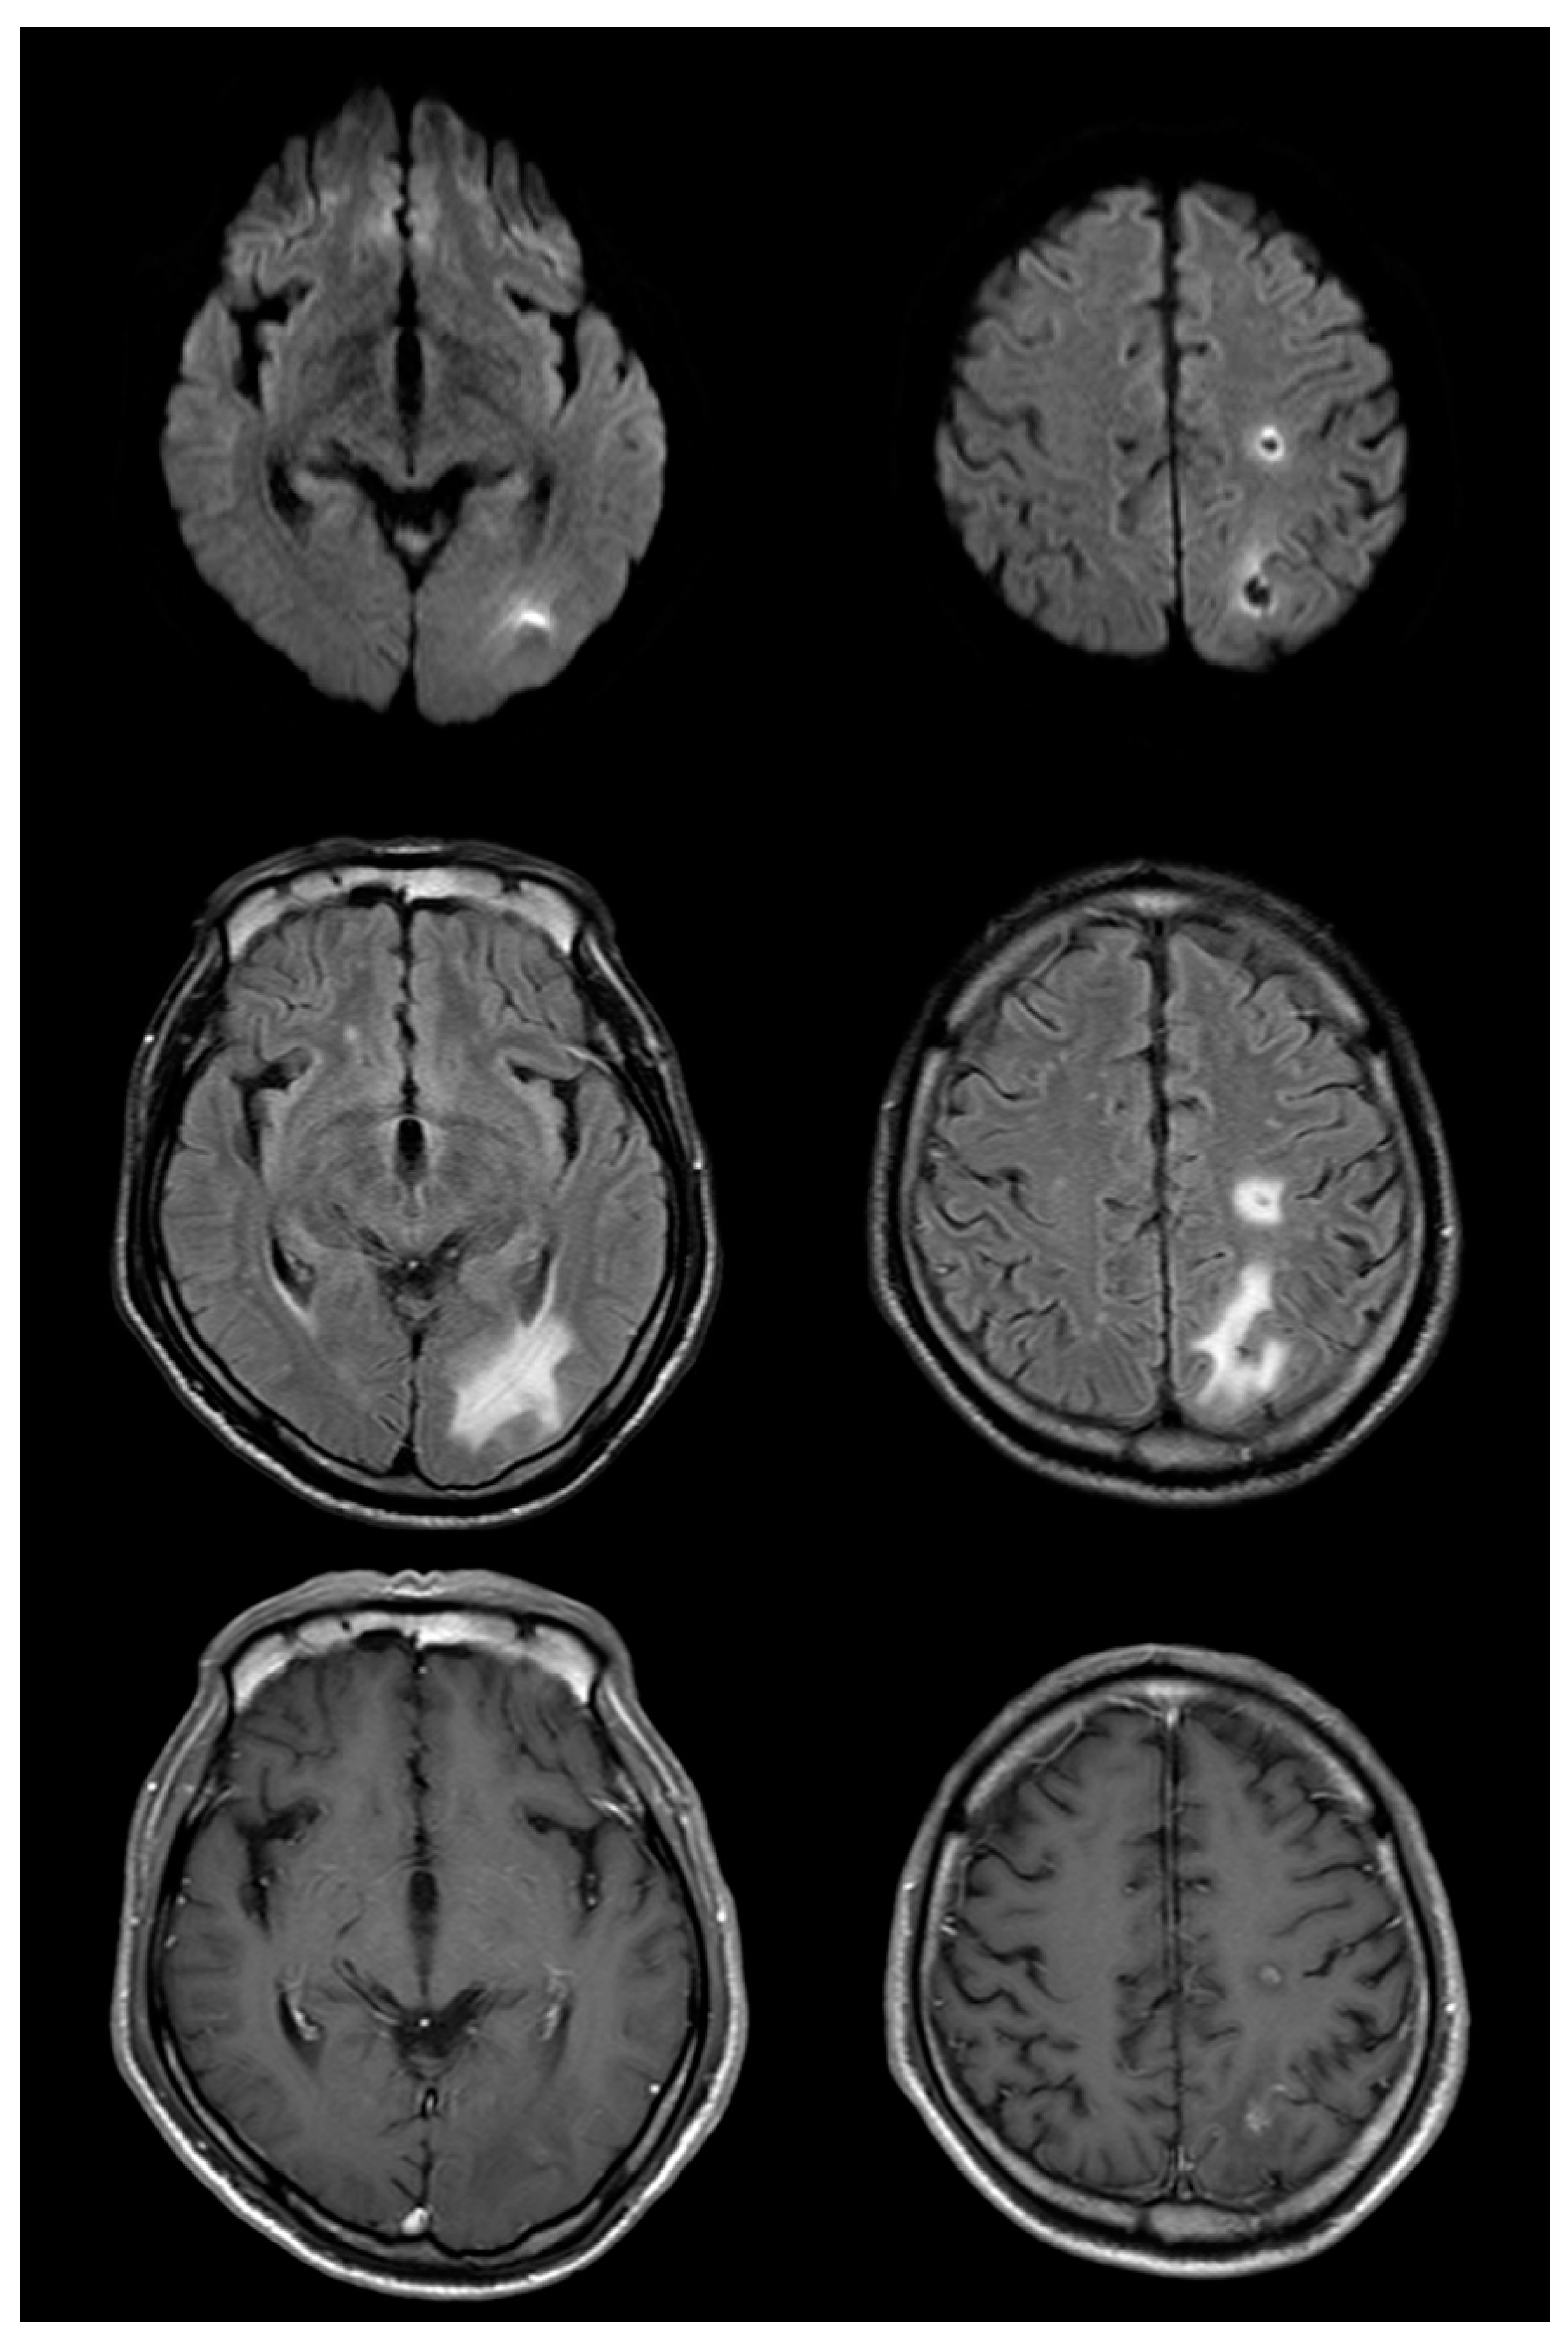

Figure 3.

Magnetic resonance imaging (MRI) on the 52nd day after symptom onset reveals a decrease in the size of lesions compared with that in the prior study (top row: diffusion-weighted imaging (DWI); middle row: fluid-attenuated inversion recovery (FLAIR); bottom row: post-gadolinium). Edema and enhancement are markedly decreased compared to that in the previous MRI; changes originally seen on DWI are evolving and resolving as well.